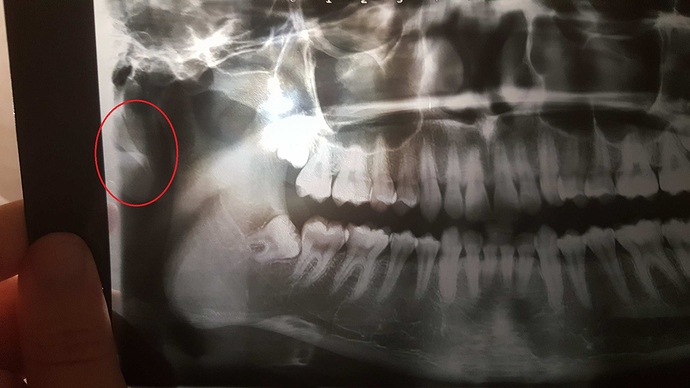

i have uploaded those two pictures of my panoramic x-ray maybe anyone please can tell if any signs that can tell if i have eagles syndrome i have had brain mri and it showed no remarkable signs of anything all doctors seem to not know well about eagles syndrome here in Egypt so i hope i can find help here

We’re not doctors/ experts on here, just people who’ve had ES ourselves, so you won’t be able to get a medical opinion, I’m afraid. But looking at the scale on the side of the x-ray, you can see that the styloid processes look to be about 3cms, so only a little over the average which a lot of doctors consider to be about 2.5cms. (Unfortunately not all doctors agree on that; some consider 3-4 cms even as ‘average’). In the Newbies Guide there’s info from research articles which states that it’s not just the length of the styloids which can cause symptoms, but also the angle they grow at. (Yours look as if they might be quite angled). Your symptoms sound quite typical- again there’s info about common symptoms in the Newbies Guide, and what could be causing them.